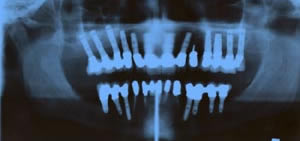

CASO FINALE

Radiografia panoramica

posizionamento 2 impianti in sede inefriore destra